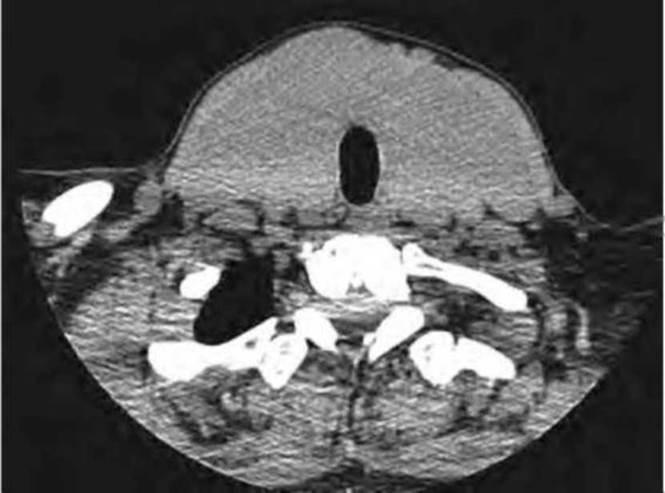

Диффузное неоднородное образование